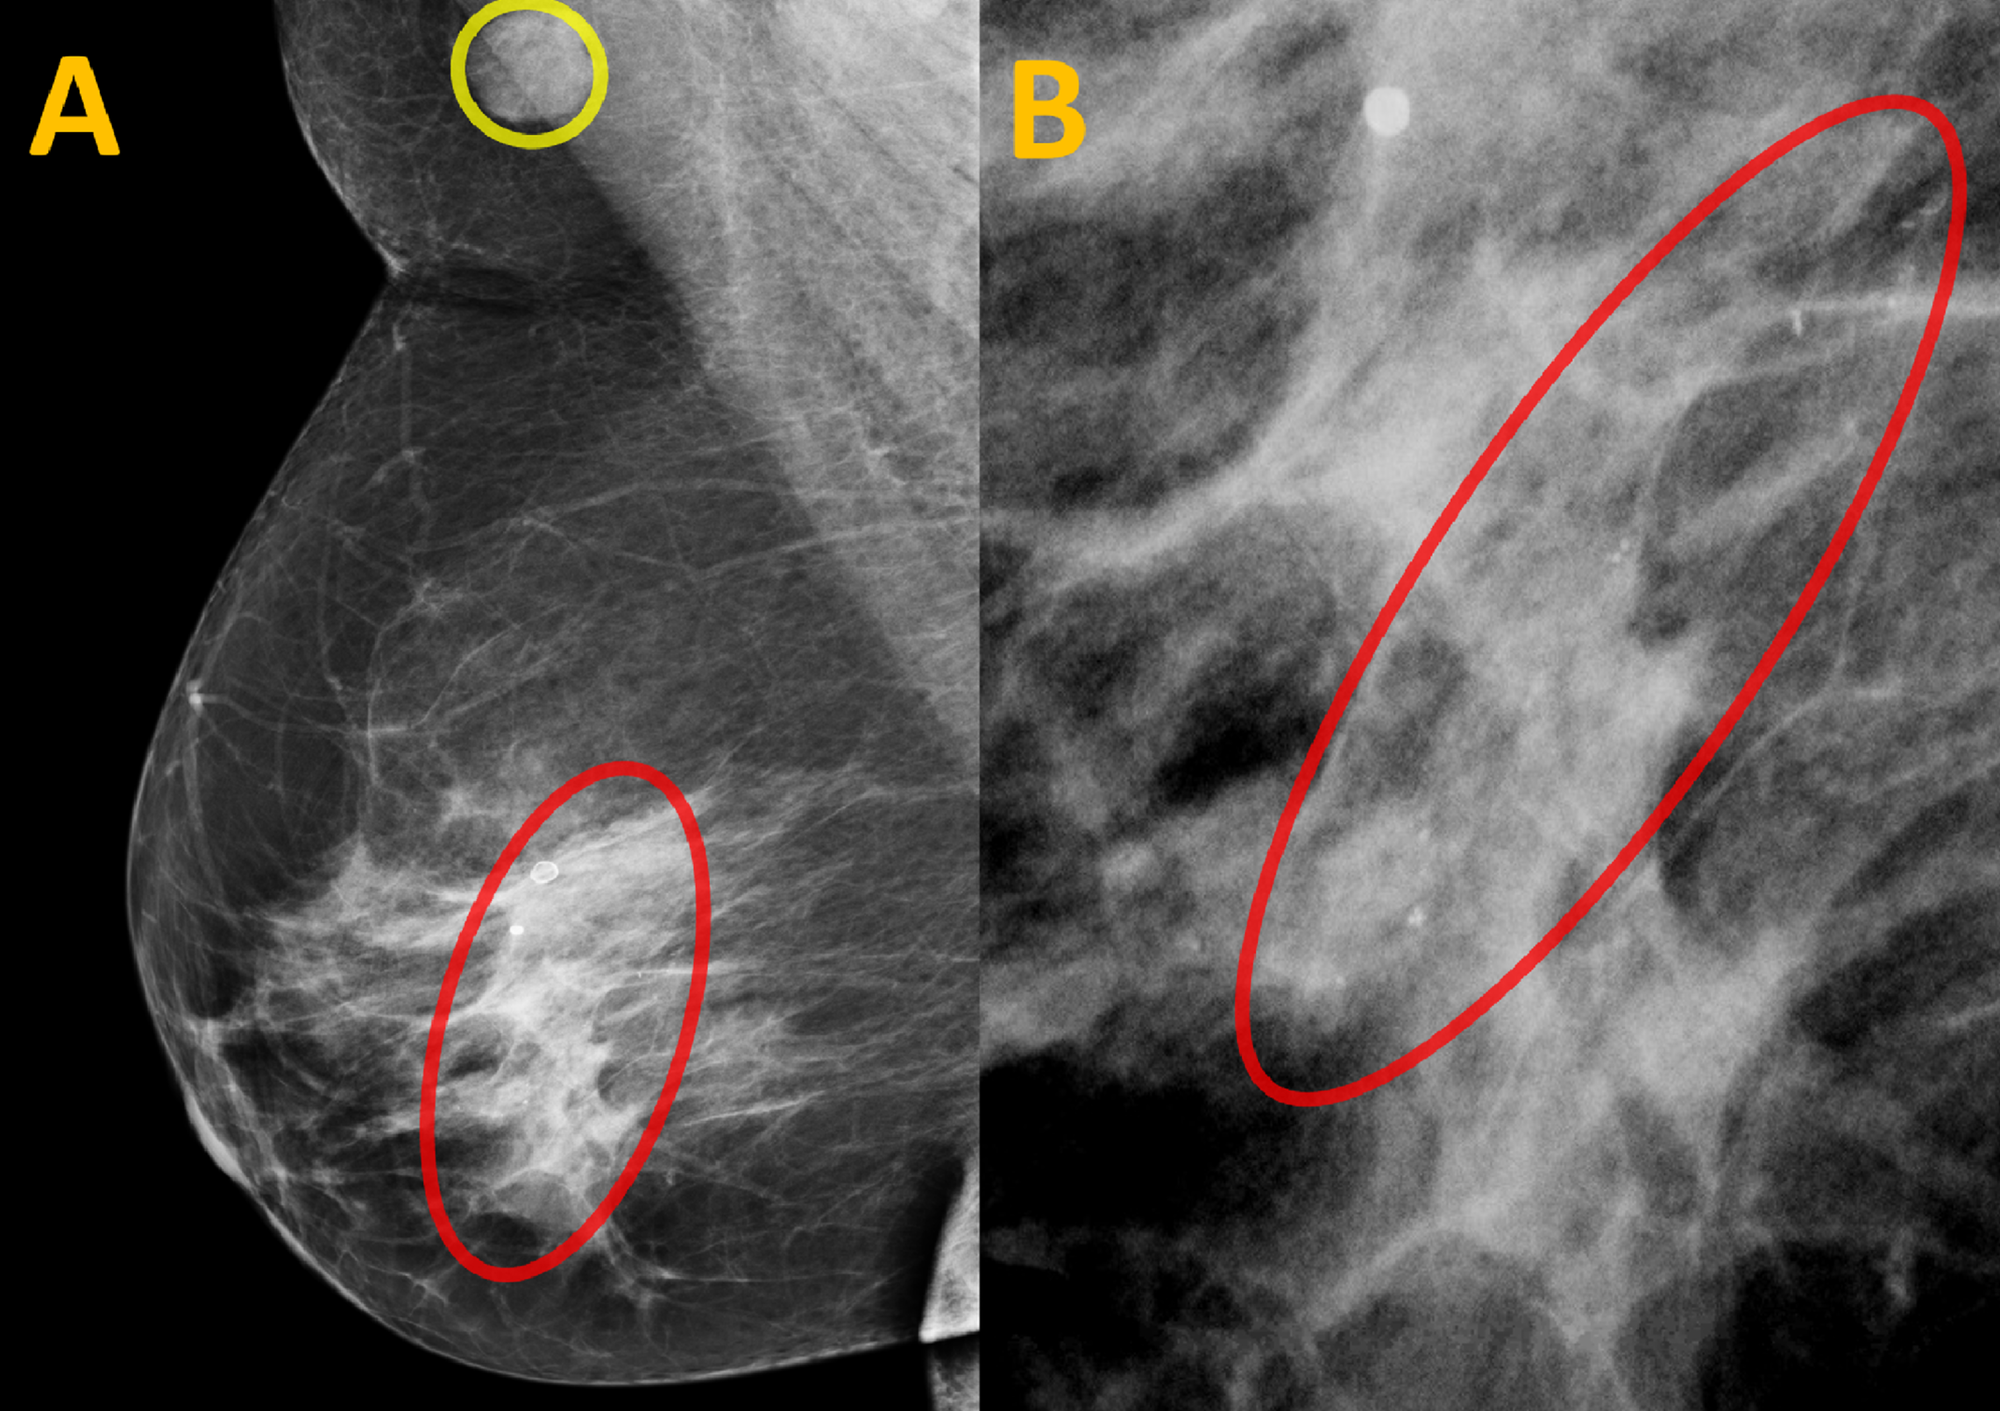

How to reduce calcification. Breast calcifications are calcium deposits that develop in breast tissue. Eating foods low in fat. While they’re usually benign (noncancerous), breast.

One of its functions is to transport excess calcium from places in. They’re common and often show up on a routine mammogram. The body controls the amount of calcium in the bloodstream very carefully.